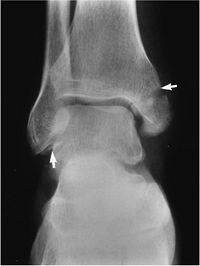

P.329

FIGURE 6-16 Pronation-abduction Stage III injuries. (A) There is a transverse medial malleolar fracture (white arrow), tibiofibular ligament tears with separation of the tibia and fibula (open arrows), and an oblique fibular fracture (black arrows). (B) Widening of the medial ankle mortise (white arrow) caused by a ligament tear with increased tibiofibular distance (open arrows) and oblique fibular fracture (black arrows).